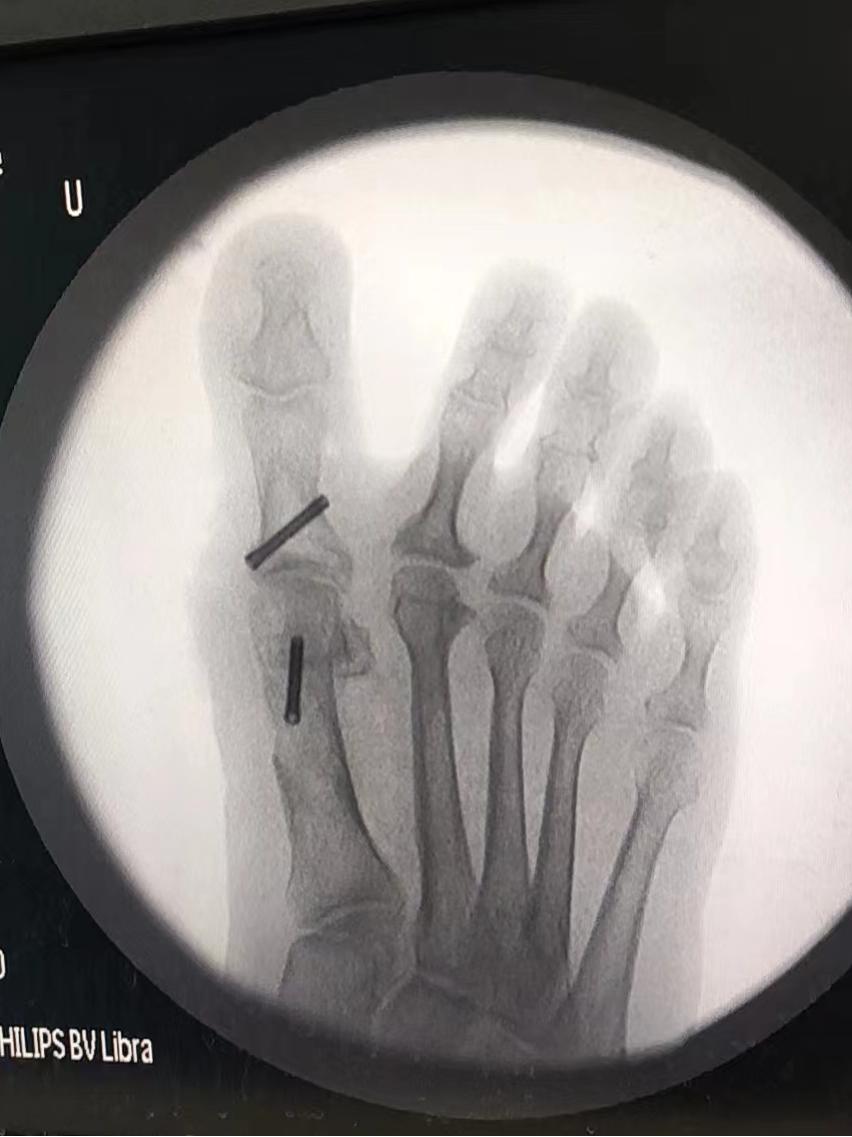

入院后,经过X片下的测量和术前相关检查后,与张阿姨进行手术沟通,拟定手术方案,最终决定针对张阿姨的情况给予拇外翻矫形术。

术后张阿姨姆囊部的疼痛及行走疼痛明显缓解,经过一段时间的休养,现已可以自由行走。“感谢你们让我彻底摆脱了拇外翻对我造成的多年困扰,现在我可以出门买菜,跳跳广场舞了”张阿姨握着医生的手激动的说。科普小知识